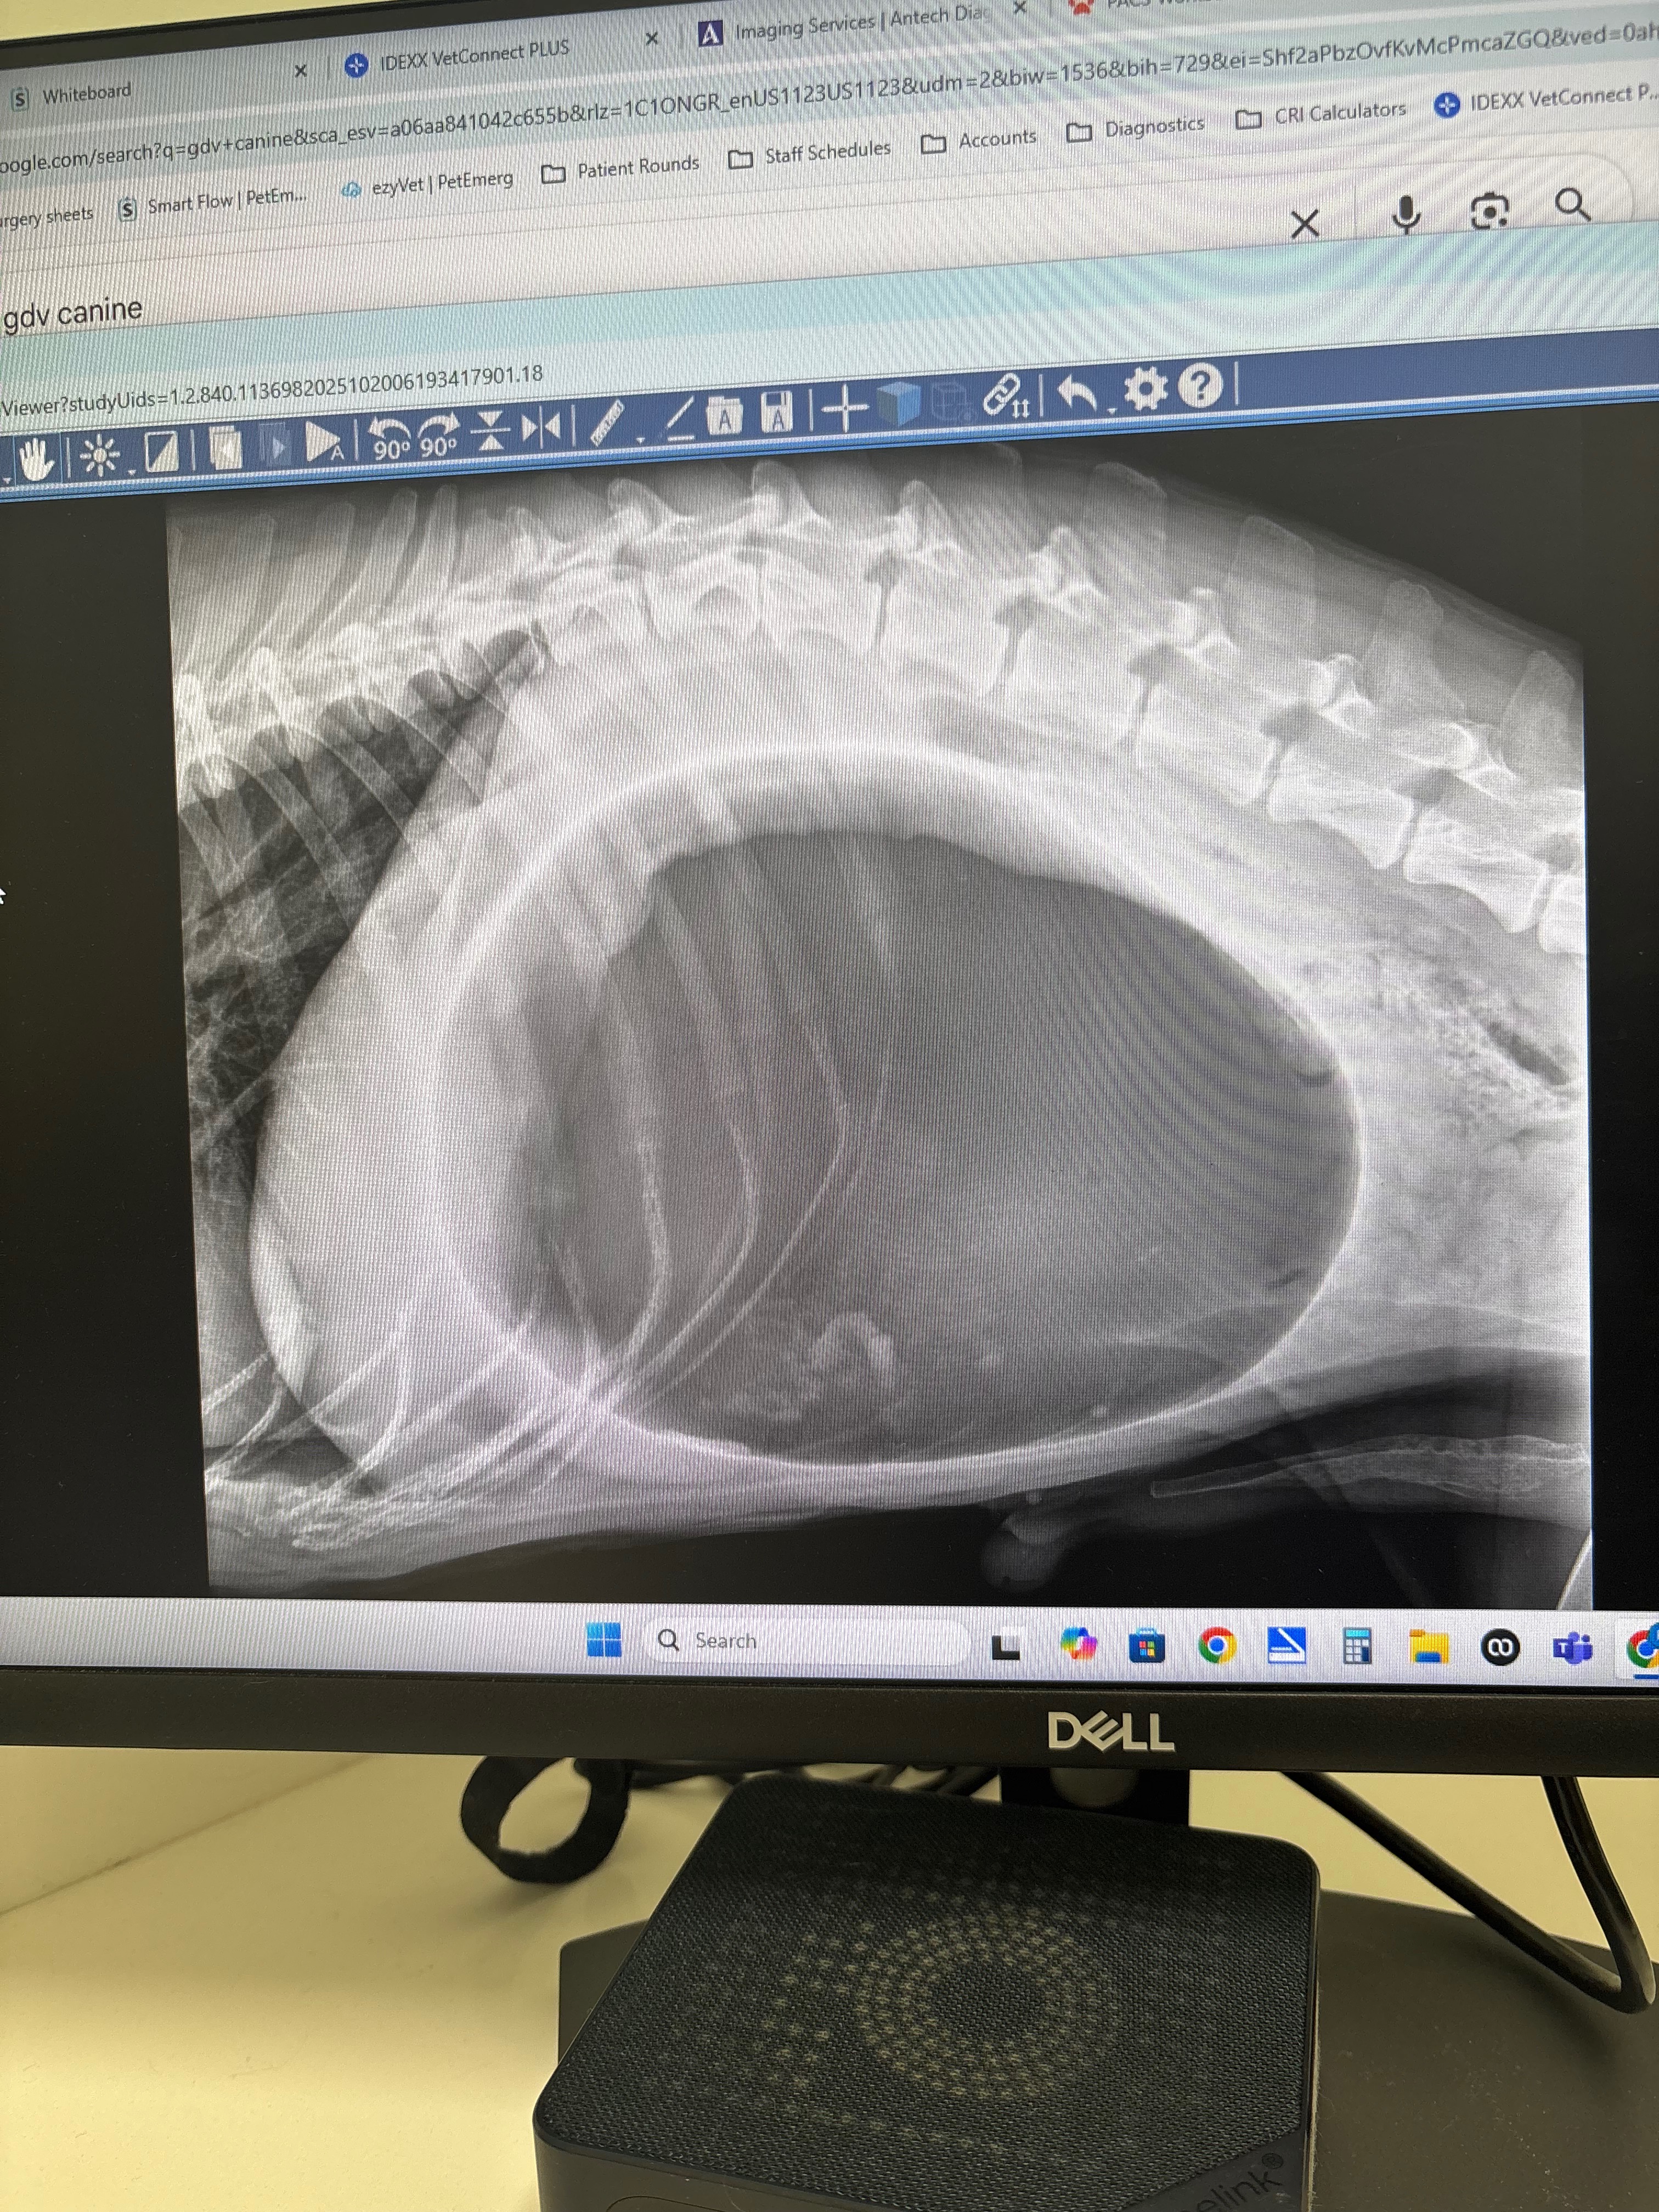

Chuck had an emergency on Monday 10/20 and had to be rushed to an emergency hospital where it was discovered that his stomach had flipped and was causing him to bloat. The only option was emergency surgery to save his life, and every minute that passed was worsening his condition. We did not hesitate and did not care about the cost and let the doctor know to proceed with surgery. Surgery went well, but his recovery was not going as planned. Chuck started to bleed from his nose and incision. It was discovered that his blood was not clotting as it should and his platelet count was low. Chuck had to spend the next 3 days being hospitalized for close monitoring and had to receive various transfusions in the hopes that we could stabilize his levels. The cost was high, but we were not going to give up and, of course, approved for him to receive all the treatment needed.